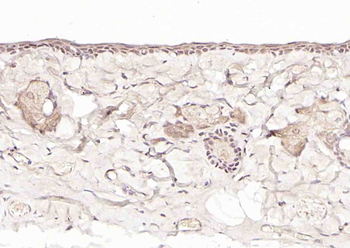

Axin1 Rabbit Polyclonal Antibody

ICC, IF, IHC-Fr, IHC-P

应用稀释比例:IHC-P=1:100-500, IHC-F=1:100-500, ICC/IF=1:100-500, IF=1:100-500